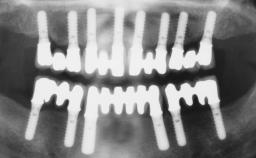

Surgical SAC classification

| SAC Level | - |

|---|---|

| Defining Characteristics | - |

| Modality | - |

| Placement Protocol | - |

| Tooth Site | - |

| Socket Morphology | - |

| Socket Integrity | - |

| Bone Volume | - |

| Anatomic Risk | - |

| Esthetic Risk | - |

| Complexity | |

| Risk of Complications | - |